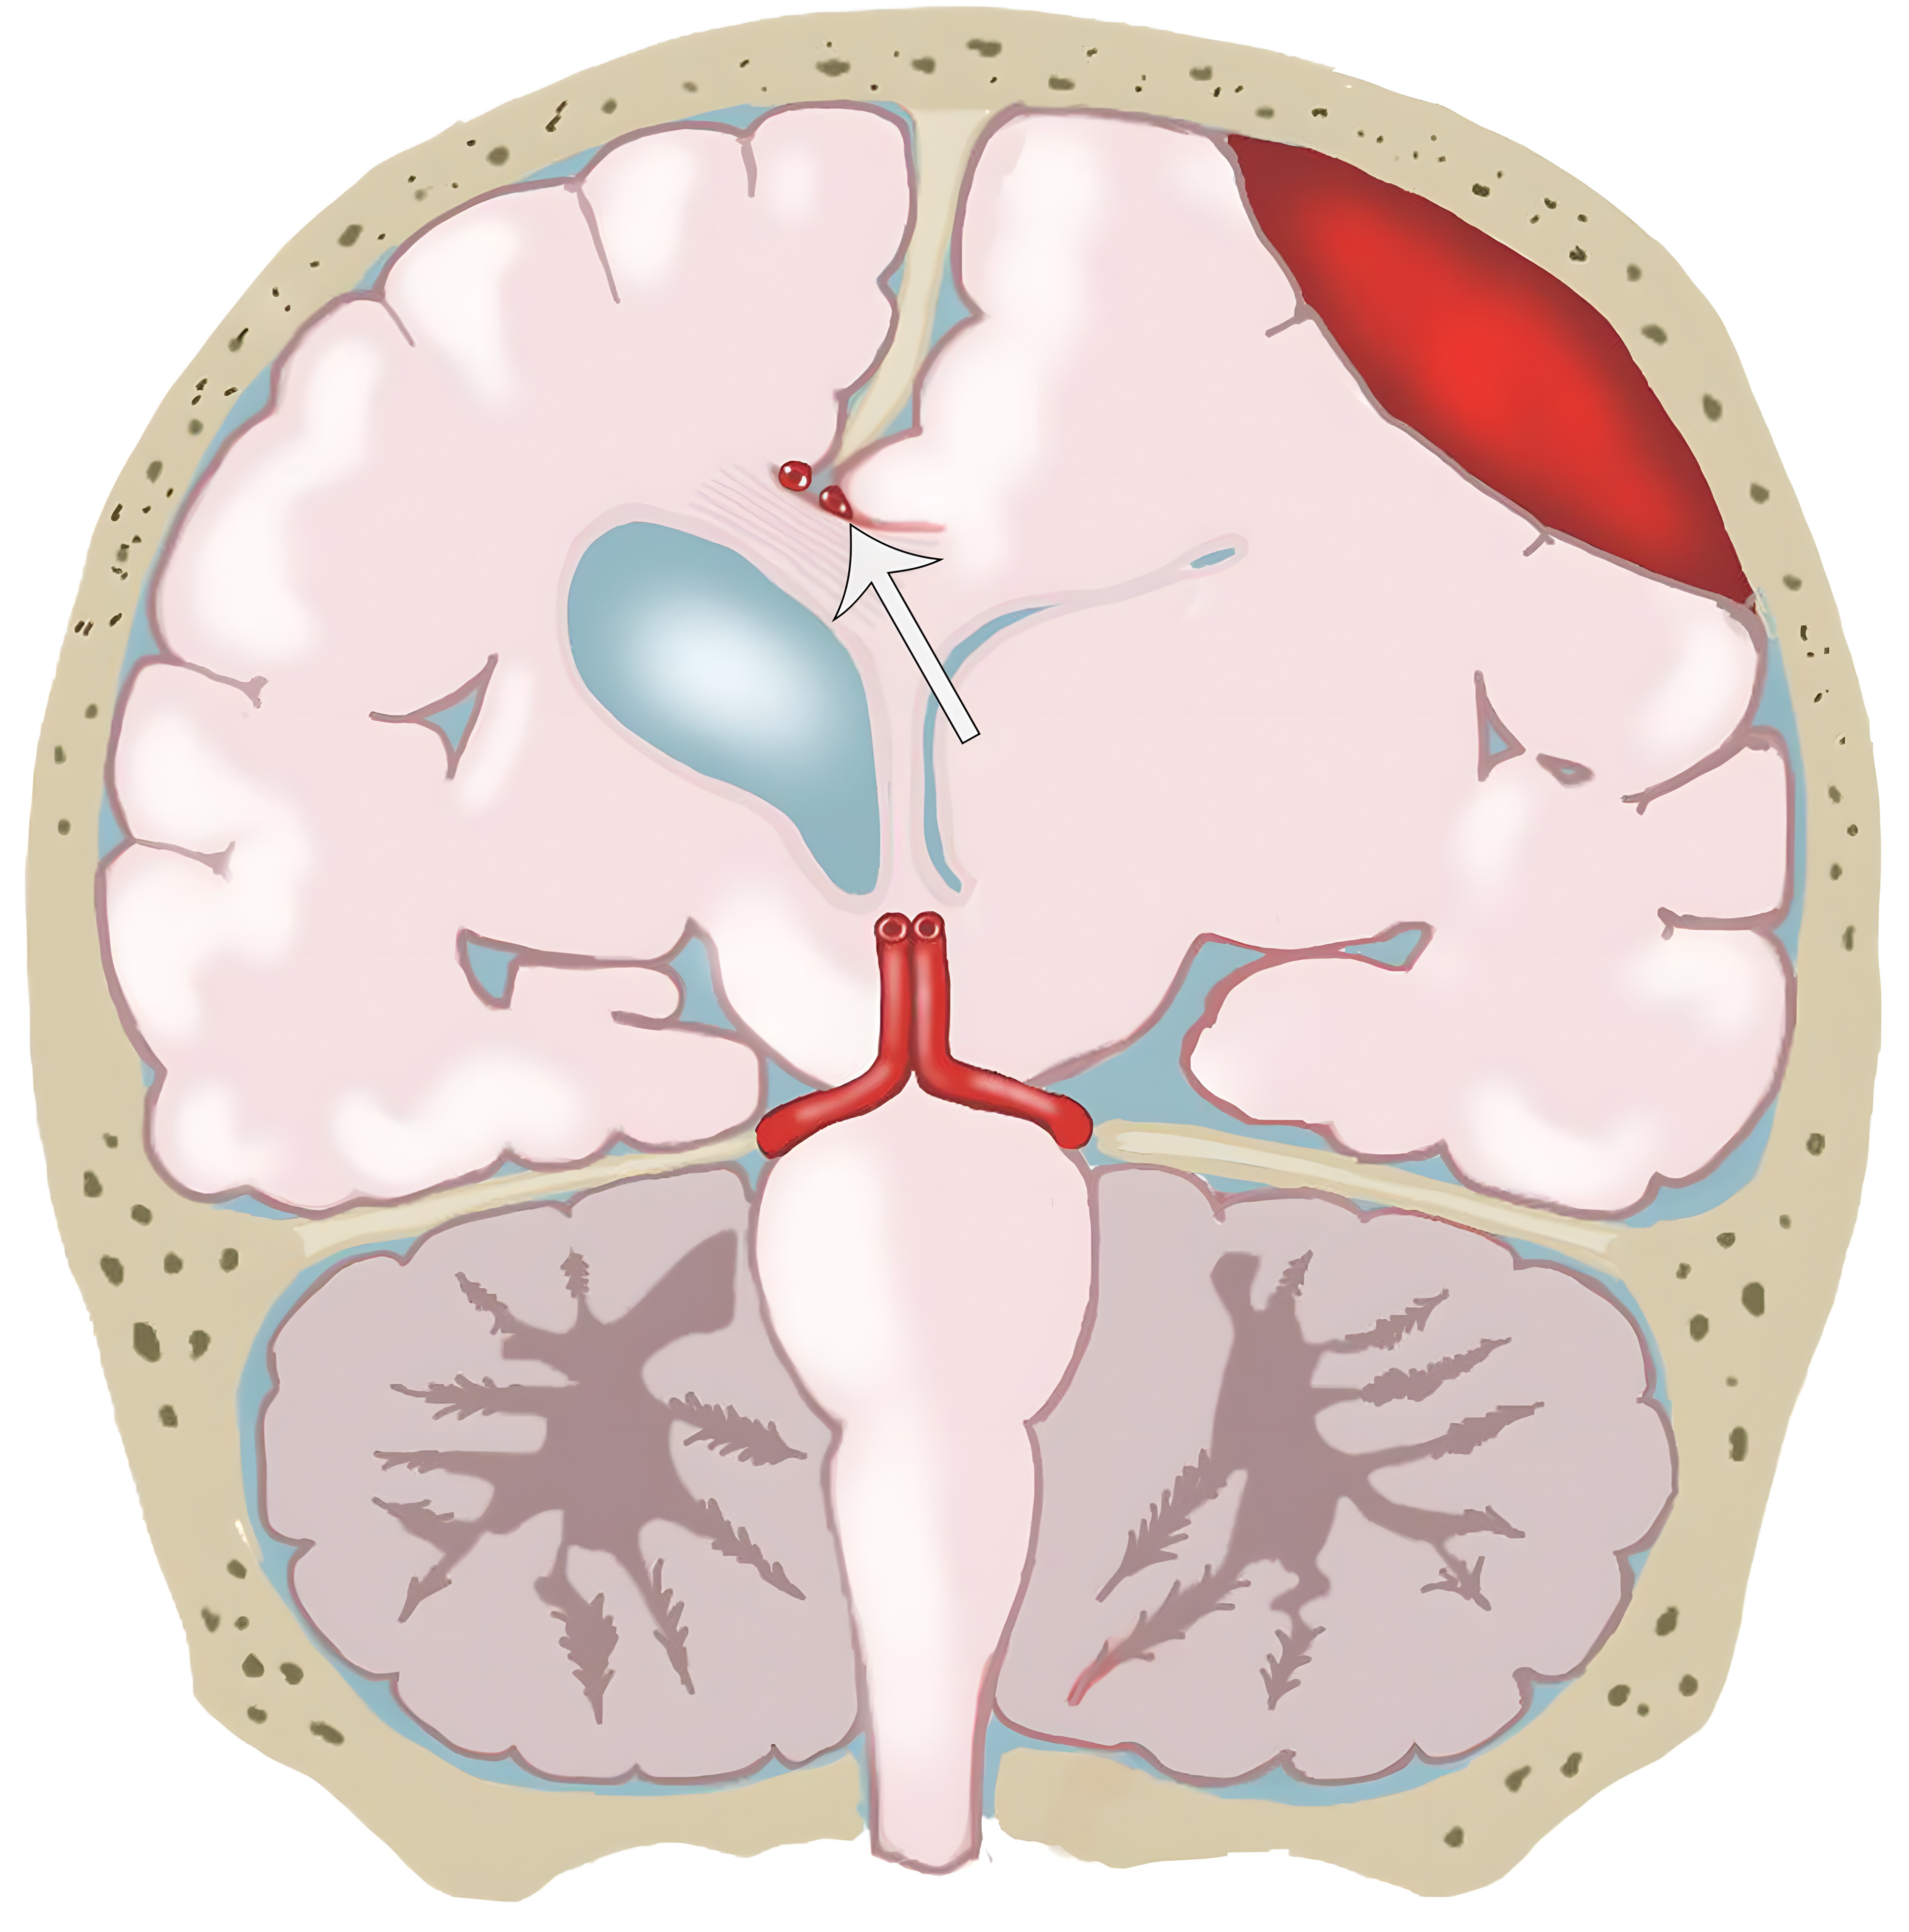

大脑镰下疝。平扫轴位CT示:右侧硬膜下血肿(*)伴混合密度影,表明处于不同时期的血液,血肿推挤使透明隔相对于中线(白色虚线)向左侧移位(白色长箭头)。右侧侧脑室受压,但是左侧侧脑室扩张。

e10b81f69aecfde7ed5f5612478dbcdc.jpeg

33岁男性,生殖细胞肿瘤脑转移患者的大脑镰下疝:冠状增强CT示大脑穹隆游离缘下方的扣带回从左向右疝入(白色弯箭头),并伴同侧胼胝体(*)的下侧移位,注意同侧脑室受压和对侧脑室的扩张(白色箭头)。

b970e936c5e18c5c1ffcf84ad6aaa810.jpeg

分房性硬膜下血肿及大脑镰下疝。左侧额叶挤压大脑镰(白色短箭头),以及蛛网膜下腔的消失。同时需要注意室间孔略向右侧移位(白色长箭头)。

17496552da14d75da4e50ca41aa734cc.jpg

由于大脑镰下疝,胼周动脉(白色长箭头)挤压至大脑镰。